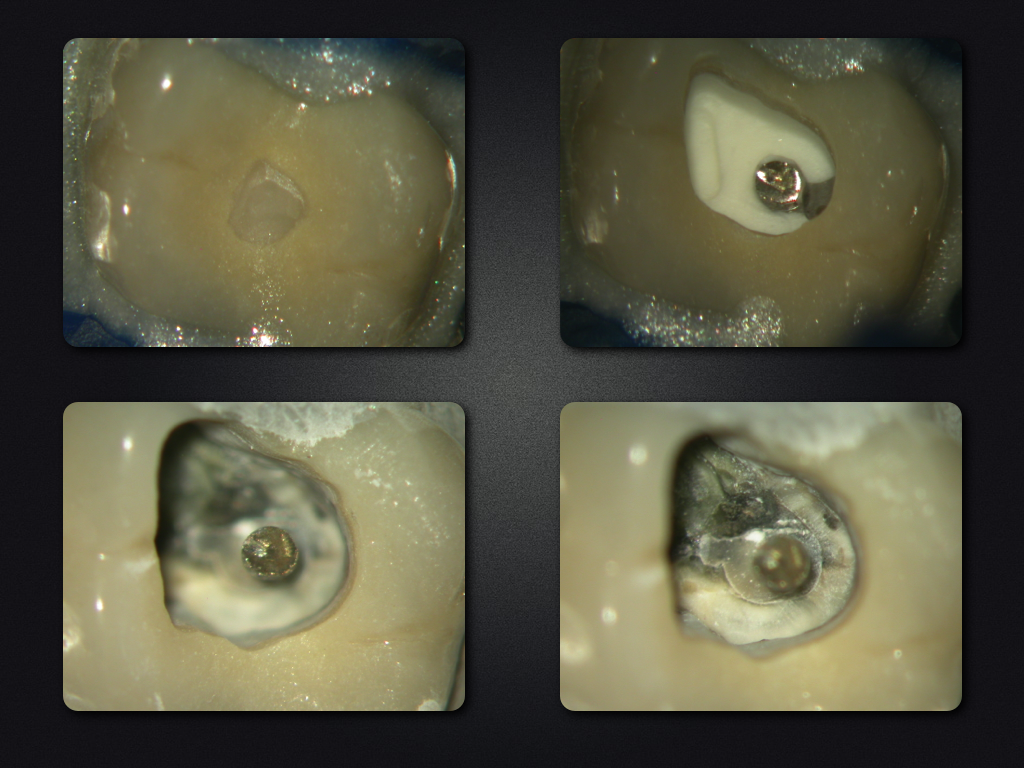

26D.002

Fette Stufe